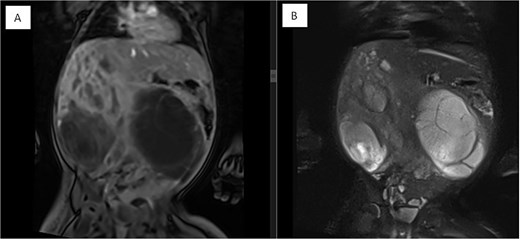

Several months later, she developed progressive abdominal distension and recurrent vomiting, prompting further evaluation. A CT scan of the abdomen revealed a large heterogeneous hepatic mass primarily occupying the right lobe, measuring 12.6 × 8.8 × 14 cm, with multicystic areas and soft tissue enhancement. MRI also demonstrated a large right hepatic lobe mass with mass effect and heterogeneous enhancement (Figs 1 and 2). Mild upper abdominal lymphadenopathy was noted (largest node 8 × 10 mm), along with a right-sided inguinal hernia. Differential diagnoses included HMH, with hepatoblastoma and undifferentiated sarcoma considered less likely. A chest CT showed mild pericardial effusion and an inflammatory appearance.

Dynamic MRI of the abdomen demonstrating a large, partially cystic, and solid lesion arising from the right hepatic lobe. (A) Axial T1 and (B) axial T2 images show the lesion’s mixed composition and internal structure. (C) Arterial and (D) portovenous phase post-contrast images reveal heterogeneous enhancement of the solid and septal components.